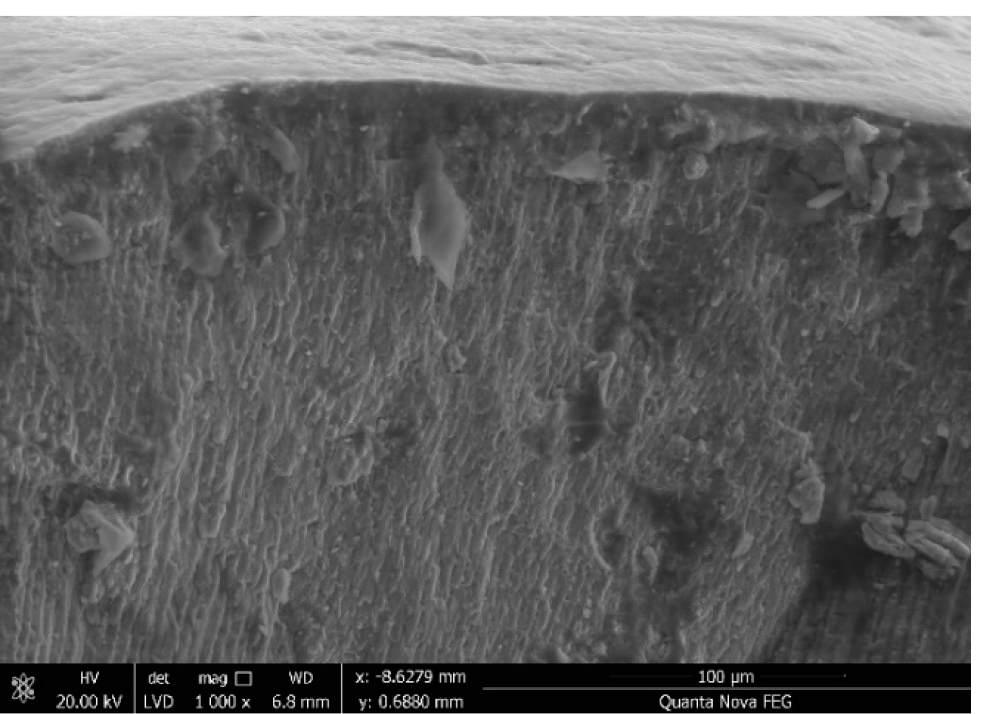

На сканирующих электронных микрофотографиях эмали выявлены эмалевые призмы (рис. 1), которые на продольных срезах имели слегка изогнутую волнистую S-образную форму, а на поперечных – вид арок. Диаметр призм, расположенных ближе к дентино-эмалевой границе, был (3,02 ± 0,30) мкм, что значительно меньше таковых в области поверхности зуба (5,45 ± 0,61) мкм. Основу эмали составляли крупные кристаллы гидроксиапатита, напоминающие вытянутые неправильные шестиугольники, между которыми сохранялись микропространства. Кристаллические структуры располагались упорядочено: в центральной части призмы лежали практически параллельно длинной оси, а в удаленных участках – веерообразно. Узкий периферический слой «оболочки» или «короны призмы» обладал меньшей электронной плотностью. В межпризменном веществе кристаллы лежали перпендикулярно кристаллам призм. Наружный слой – конечная эмаль – чрезвычайно вариабельный по строению: в одних участках обнаружены плотные беспризменные зоны, в других эмалевые призмы достигали самой поверхности зуба.

При сканирующей электронной микроскопии поверхность эмали представлена характерными образованиями в виде неровностей и мелких вдавлений (ямок), создающих структуру на подобии сот. Начальная эмаль – внутренний слой толщиной (7,50 ± 2,82) мкм – не содержала призм. В области дентино-эмалевого соединения встречались участки с большим содержанием белков и слабо минерализованными эмалевыми призмами: эмалевые пластинки, пучки и веретена.

Рис. 1. Эмаль (резец). Сканирующая электронная микрофотография (×1000)